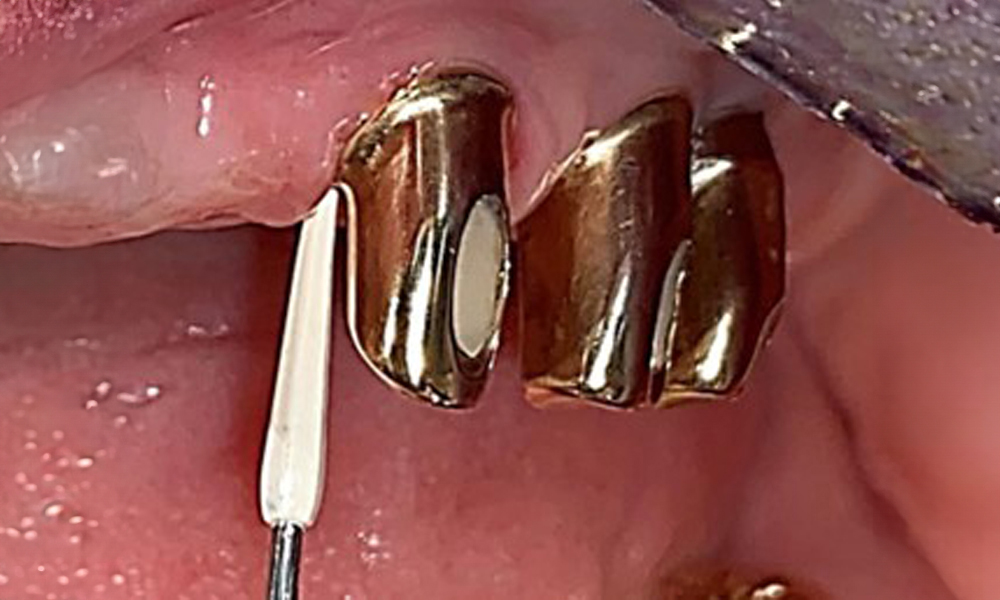

The patient was fitted with a combined removable maxillary telescopic prosthesis more than 25 years ago (Fig. 1, Fig. 2, Fig. 3) and is very happy with her dentures. The patient has an adequate fixed denture for the mandible (Fig. 4).

The dental findings are as follows: Combined removable implant and tooth-supported telescopic prostheses on implants 15, 13, 21, 23, 24, 25 and tooth 11 (Fig. 1, Fig. 2, Fig. 3). The patient was fitted with a fixed mandibular denture. Adequate bridges were present over 37 to 34 and 45 to 47 (Fig. 4), the crown margins were intact and there were no active caries. A composite filling with a marginal gap was present on tooth 43. There was mandibular gingival recession, exposing 1 to 3 mm of root surface. This also applies to 11.

The periodontal status should be thoroughly examined once a year. This examination provides comprehensive documentation of the periodontal and implant findings, including pocket depths, periodontal recession and furcation involvement. This will ensure a rapid response to any potential progression of the mucositis, gingivitis, periodontitis or peri-implantitis. Implant probing using a plastic probe is recommended. In the present case, a mesial probing depth of 4 mm was detected mesial to implant 23. No suppuration or bleeding was detected, indicating the absence of peri-implantitis.